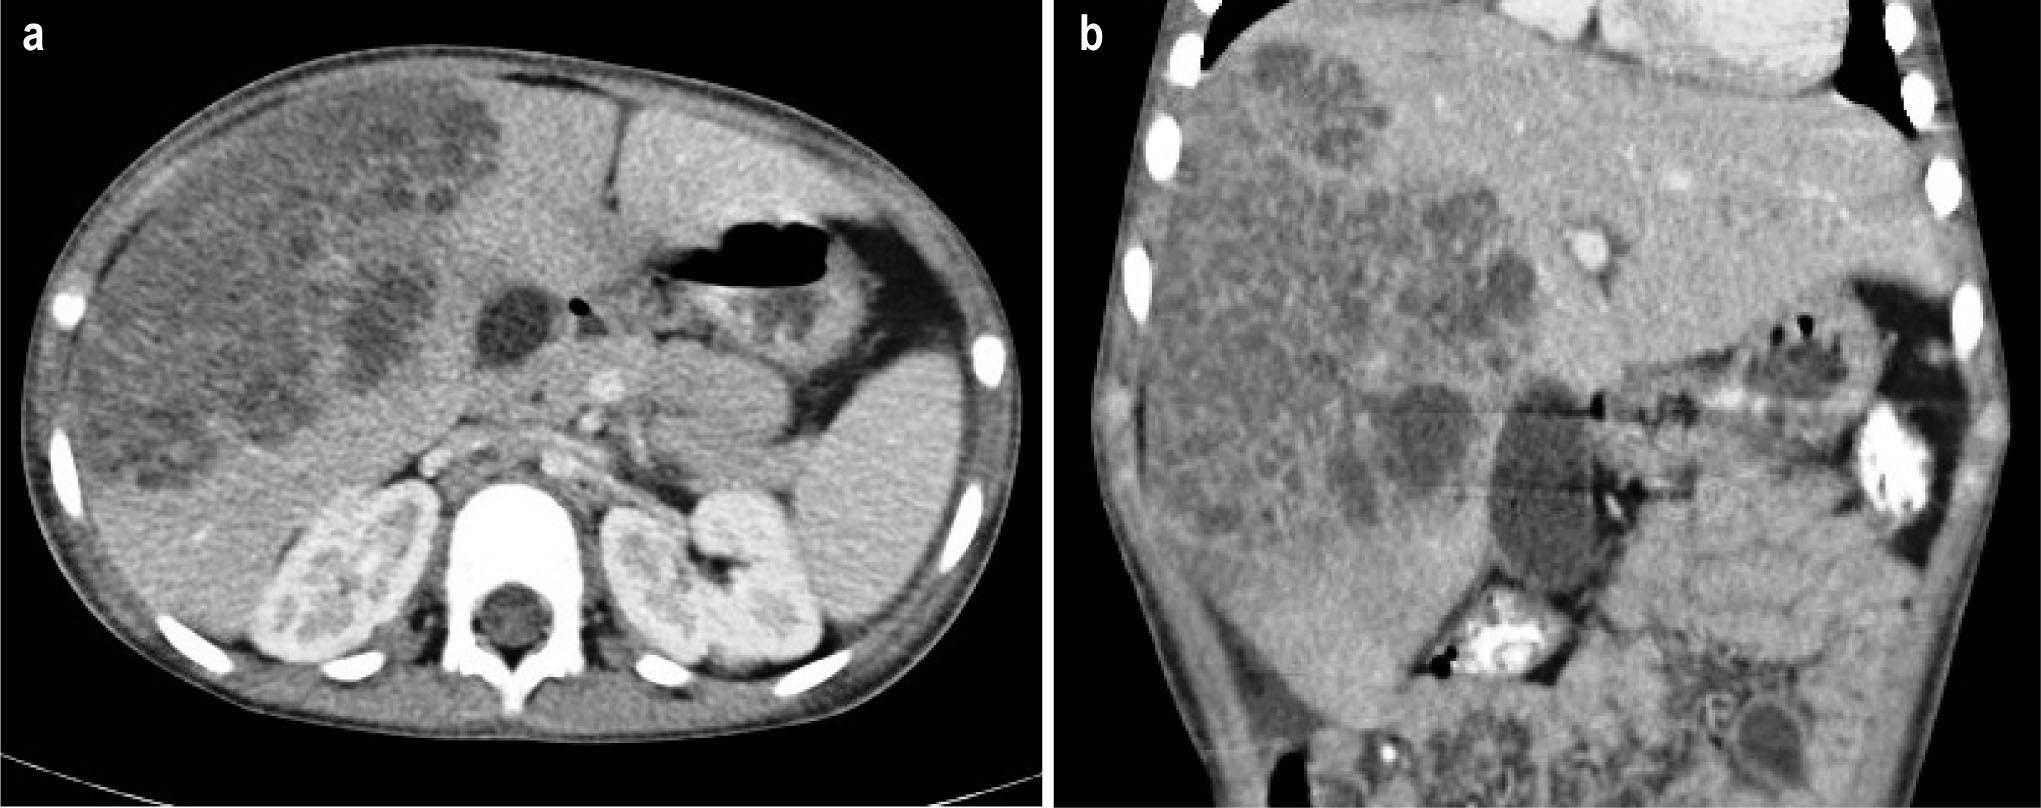

Fig. 1